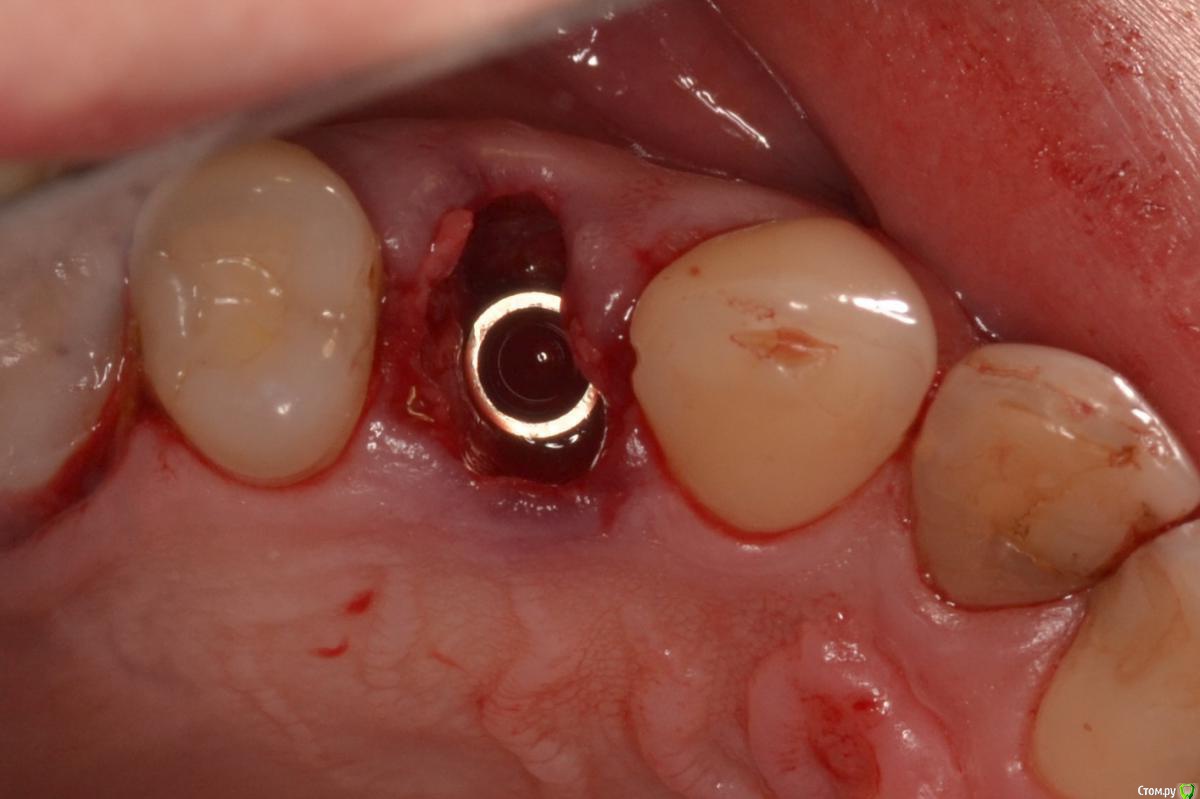

Военный Врач Опубликовано 5 апреля, 2016 Поделиться Опубликовано 5 апреля, 2016 Удалили и прикрутили. между имплантацией и снятием швов 9 суток. лунку закрывал тканями с бугра 18 Ссылка на комментарий

Военный Врач Опубликовано 5 апреля, 2016 Автор Поделиться Опубликовано 5 апреля, 2016 Торк не позволил ФДМ поставить?торк очень низкий. не будем торопиться Ссылка на комментарий

Военный Врач Опубликовано 5 апреля, 2016 Автор Поделиться Опубликовано 5 апреля, 2016 Как приятно читать надписи на родном языке))) И Саш, может стоило чуточку глубже поставить?там и так очень глубоко. просто красиво фотографировать так и не научился... Ссылка на комментарий